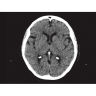

Позволяет проводить комплексные исследования всех анатомических зон, включая нейровизуализацию, ангиографию, исследования органов грудной и брюшной полости. Особенно эффективен для раннего выявления онкологических заболеваний.